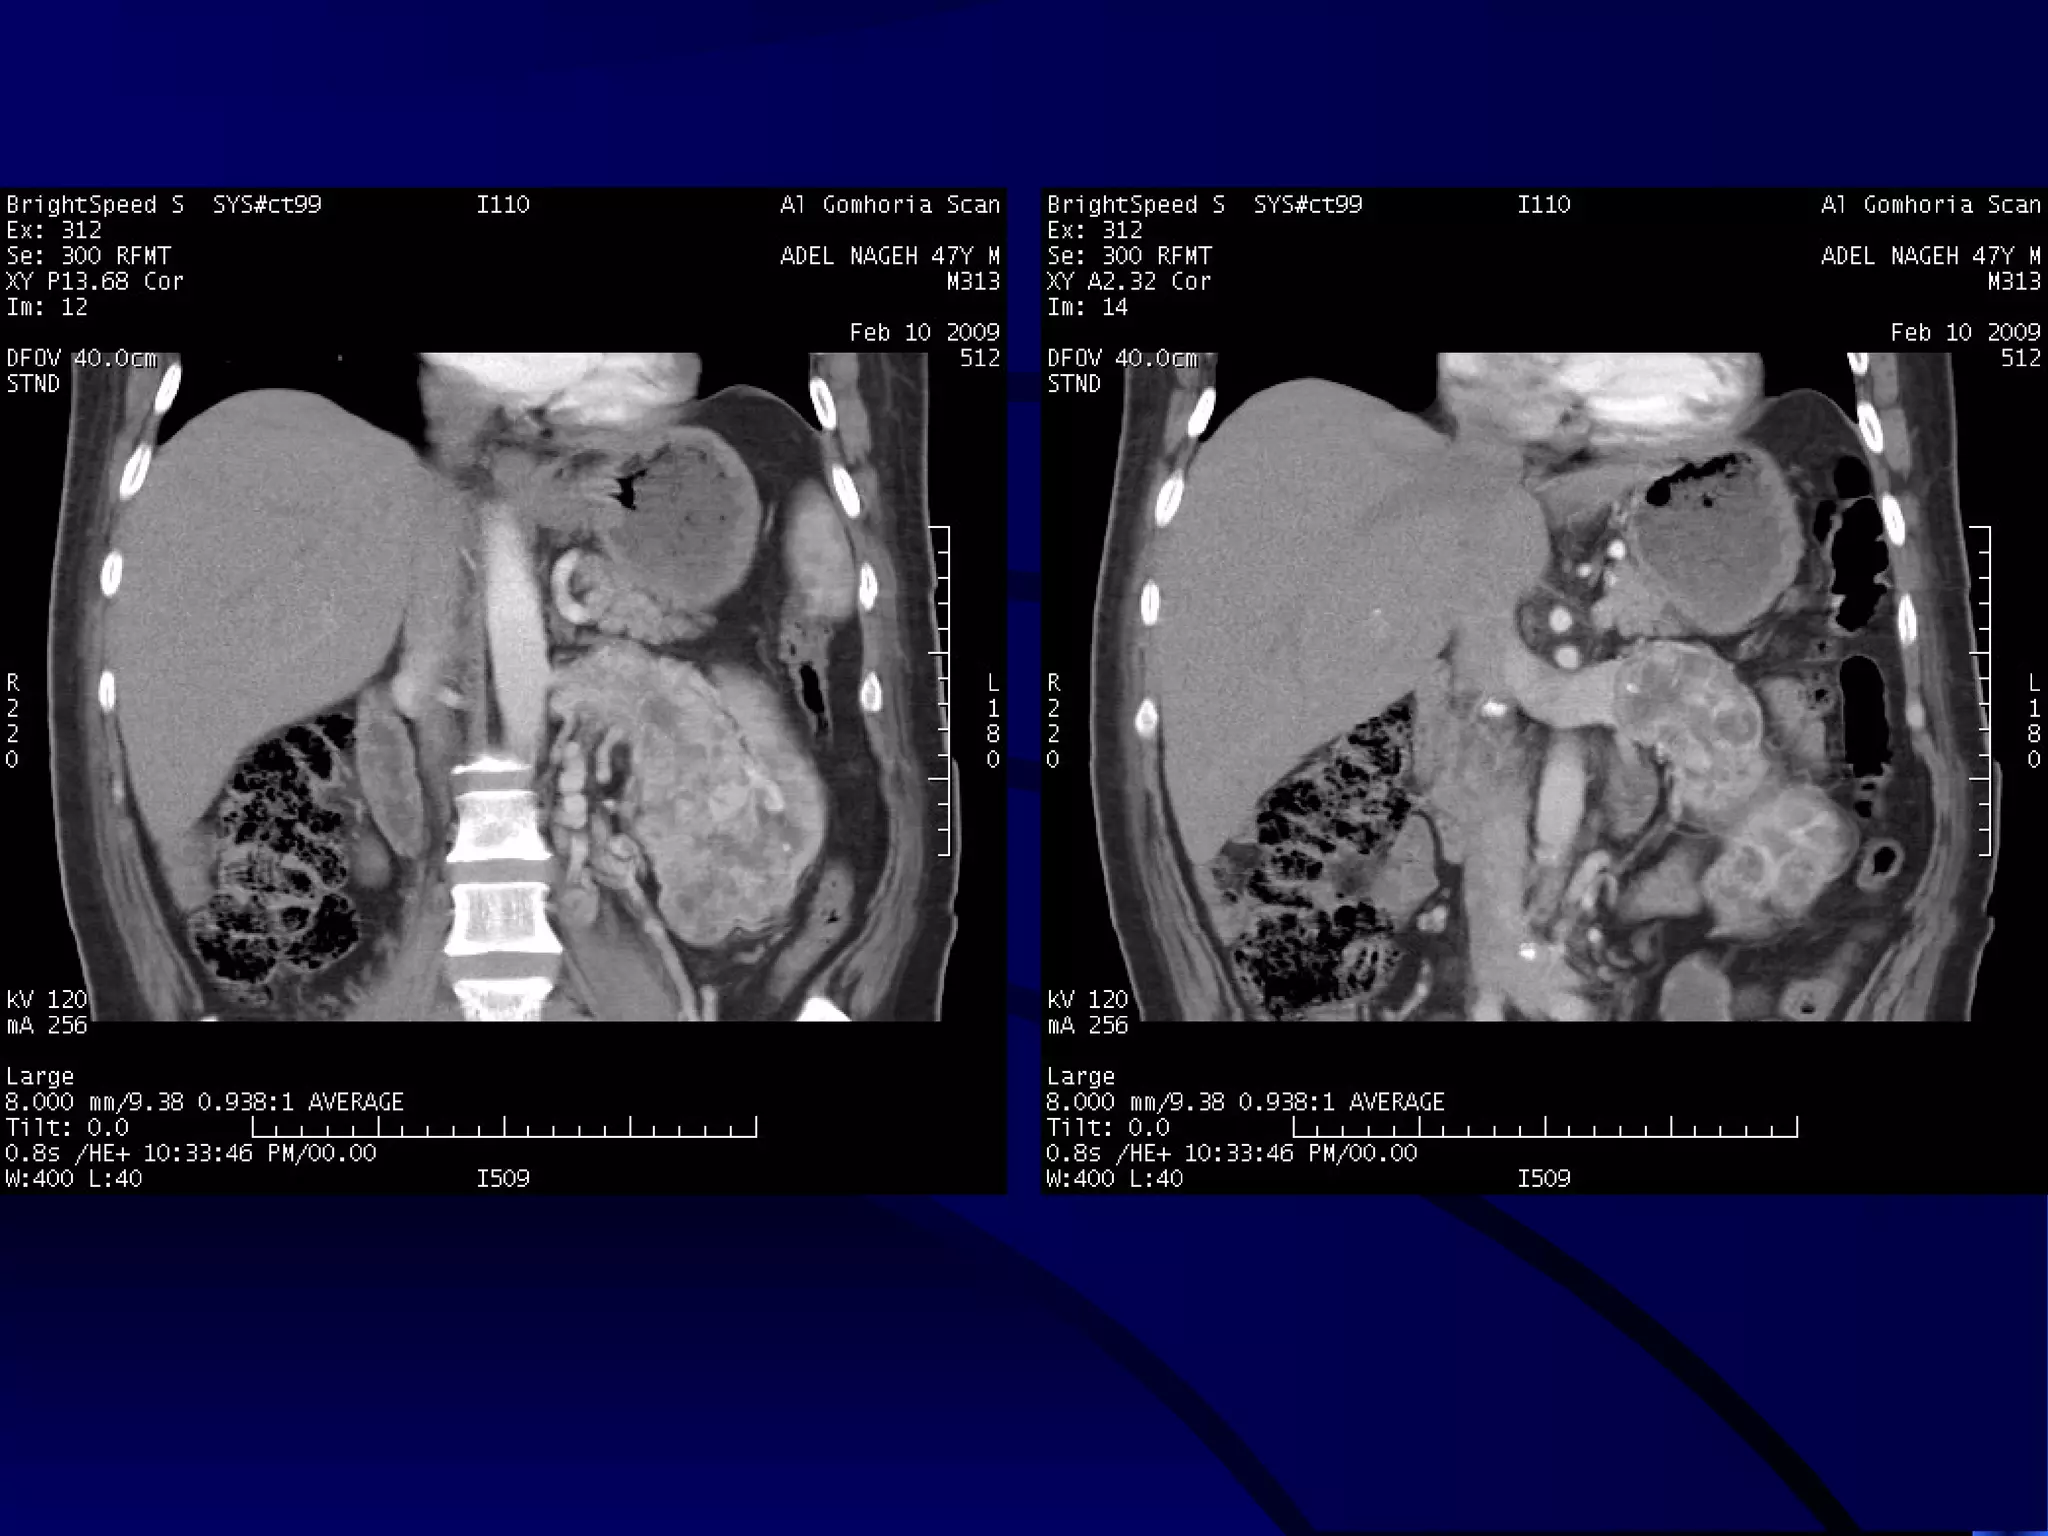

SOLID PARAPELVIC MASS

CLEARLY DEMONSTRATED

IN CORONAL IMAGES